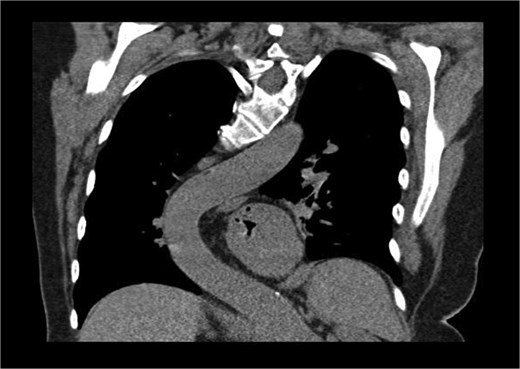

A 71-year-old female was referred to the heart team for elective minimally invasive MVR and septal myectomy. She presented with severe mitral regurgitation and hypertrophic obstructive cardiomyopathy (HOCM). Her body surface area was 1.51 m2, and BMI was 29.42. Critically, her scoliosis had a Cobb angle of 80° (Fig. 1), qualifying as extremely severe.

Coronal computed tomography (CT) with measurement of the cobb angle.